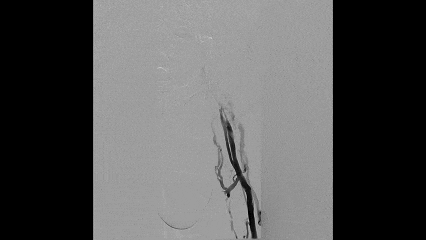

初始操作

超声引导下穿刺左侧腘静脉置入鞘管

行左下肢静脉及髂静脉造影

2

血管通路建立

尝试通过腘静脉、股浅静脉、髂股段静脉病变

发现股浅静脉近端闭塞,通过侧支与股深静脉沟通

髂静脉闭塞,盆腔侧支静脉形成